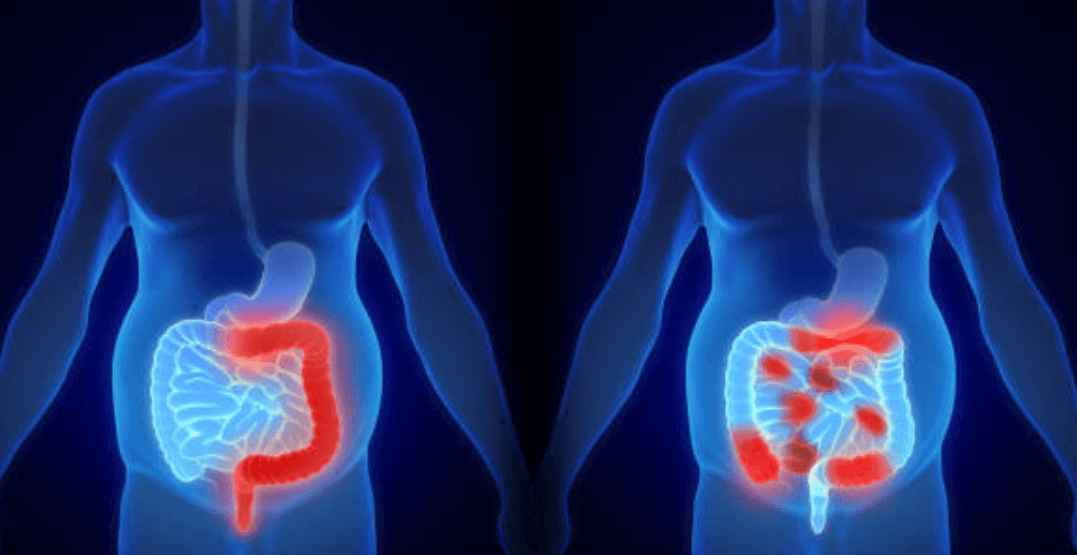

크론병은 소화기관의 만성적인 염증으로 인해 장이나 직장의 어느 부분에서든 발생할 수 있는 질환입니다.

이러한 염증은 장관벽을 손상시키고, 다양한 증상을 유발할 수 있습니다.

크론병은 장의 부위에 따라 발생하는 질환으로, 증상과 심각도가 다양합니다.